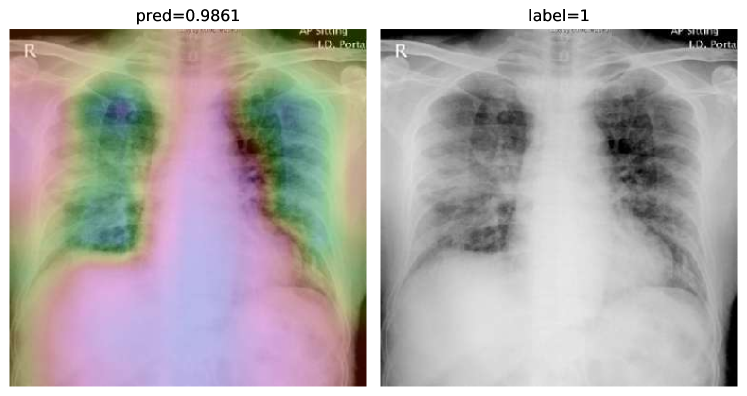

While text removal methods can prevent overfitting, we can simply force the model to look into the lungs in order to address both problems in one effort. To accomplish this task, a U-Net based segmentation illustrated in Fig. 4 is applied to the input images before enhancements. Visualization results for COVID-CXNet with the ROI-segmentation block are shown in Fig. 18.

Figure 18: Grad-CAM visualization of the proposed model, trained with lung-segmented CXRs, over sample cases.

A figure with more Grad-CAMs is attached in Appendix B. From Fig. 18, it can be observed that COVID-CXNet with ROI-segmentation has delivered superior performance regarding the localization of pneumonia features. Worthwhile to mention that image augmentation is expanded by adding zoom-in, zoom-out, and brightness adjustment. Label smoothing is also applied to the loss function.

The proposed method has shown a negligible drop in metric scores; accuracy is decreased by 0.42%, and f-score is declined by 0.02. This decrease is a result of training with a larger dataset and accurately segmented ROIs, which means it has become more robust against unseen samples. There is a trade-off between catching good features and higher metric scores; while better features result in a more generalized model, high metric scores may indicate overfitting.